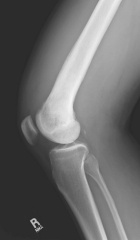

Case 6

T.C. - 40 year old male with a painful and enlarging thigh mass

Zoom image: Radiological image Radiological image.